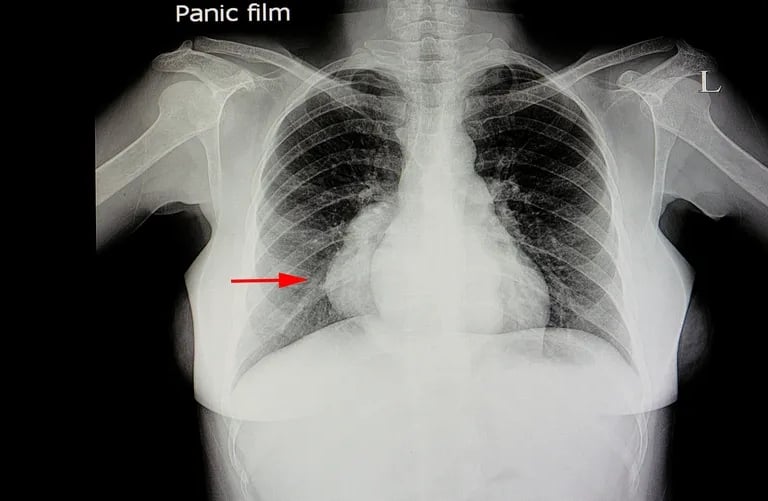

Mediastinal muayene: venöz dolgunluk, SVC sendromu bulguları, stridor/nefes darlığı.

Metabolik olarak aktif tümör dokusunun (florodeoksiglikoz - FDG tutulumu) şeker tüketimini gösteren PET-CT, teşhis algoritmamızın keskin nişancısıdır.

LR+ : ~9.5 (Pozitif bir PET, lenfoma ihtimalini dramatik şekilde artırır).

LR- : ~0.05 (FDG tutulumu yoksa, agresif lenfoma ihtimalini neredeyse sıfıra indiririz).

Kritik Kriter: Deauville Skoru (5 Nokta Skoru):[5] PET tutulumunu mediasten ve karaciğer tutulumu ile karşılaştıran standart bir dildir.

Deauville 1-3: Negatif (Tedaviye yanıt veya reaktif tutulum).

Deauville 4-5: Pozitif (Aktif tümör veya progresyon).